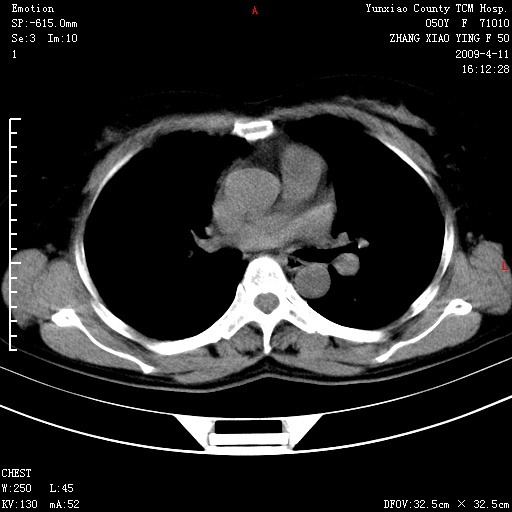

标题: CT19324:胸闷1周伴咳嗽 [打印本页]

标题: CT19324:胸闷1周伴咳嗽

病灶周围肺纹受压移位走行较柔和,余肺里实质均匀,纹理如常,肺间质无显著纤维化,支持考虑孤立性肺囊肿

考虑胸膜下肺大泡。

考虑右肺中叶肺囊肿。